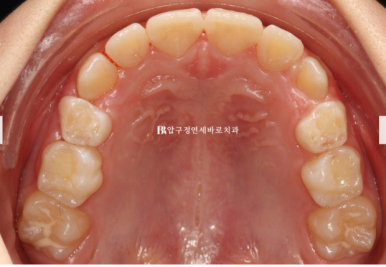

22.11.23

병원에 처음 온 날 모습입니다.

문제점을 나열해보자면

과개교합 (앞니가 깊게 물림)

덧니 (삐뚤빼뚤)

후속 영구치가 나올 공간 부족

그리고 아이의 개인적인 문제점은 당장 한달뒤에 외국에 나가 6개월 후 귀국

이런상황들에 맞춰 치료계획을 만들었습니다.